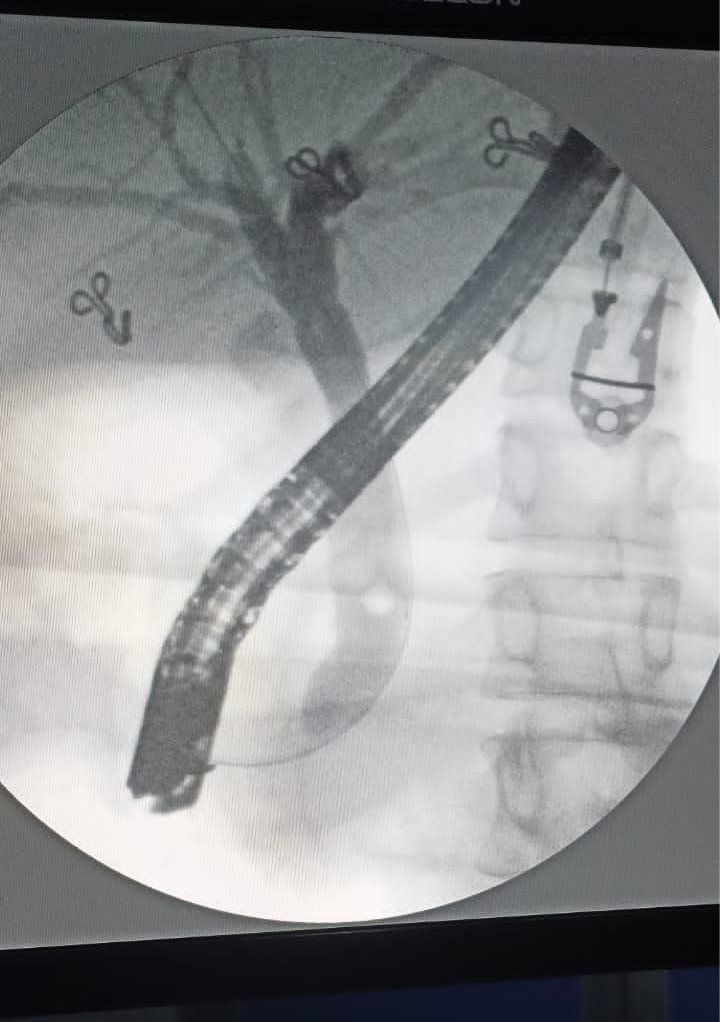

Gallstone in Pregnancy, leading to Jaundice

21 years old lady, who has recently delivered a baby, has come to the hospital with history of Jaundice. On evaluation, LFTs showed cholestatic pattern. USG done was suggestive of dilated CBD with IHBRD. EUS done suggestive of stone in the distal CBD. ERCP was done with successful removal of CBD stone. The entire procedure was done in 25 minutes without any complications.

Conclusion: Cholesterol gallstones are common in pregnancy and can lead to obstructive jaundice if its slips down into the CBD. EUS is an accurate imaging modality and can be alternative to MRCP. ERCP is a minimally invasive modality and can be curative.